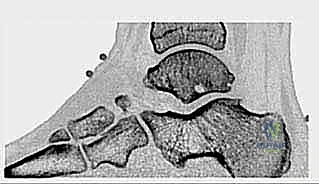

1. متلازمة انحشار الكاحل الخلفي والعظم الزائد (Os Trigonum Syndrome)

تُعد هذه المتلازمة من أكثر الأسباب شيوعاً، خاصة لدى الرياضيين (لاعبي كرة القدم) والراقصين (الباليه). العظم الزائد (Os Trigonum) هو عظم إضافي خلقي صغير يقع خلف عظم الكاحل (Talus). في الحالات الطبيعية، قد لا يسبب ألماً، ولكن مع الثني القسري المتكرر للقدم نحو الأسفل (Plantar Flexion)، ينحشر هذا العظم بين عظم الظنبوب وعظم العقب، مما يؤدي إلى التهاب شديد وتمزق في الأنسجة المحيطة به.

* الأشعة السينية (X-rays): بوضعيات خاصة (Lateral view) لرؤية العظم الزائد (Os Trigonum) والنتوءات العظمية وتضيق المسافات المفصلية.

* الأشعة المقطعية (CT Scan): تُستخدم في حالات معينة لعمل خريطة ثلاثية الأبعاد للكسور القديمة أو التكلسات العظمية المعقدة قبل الجراحة.